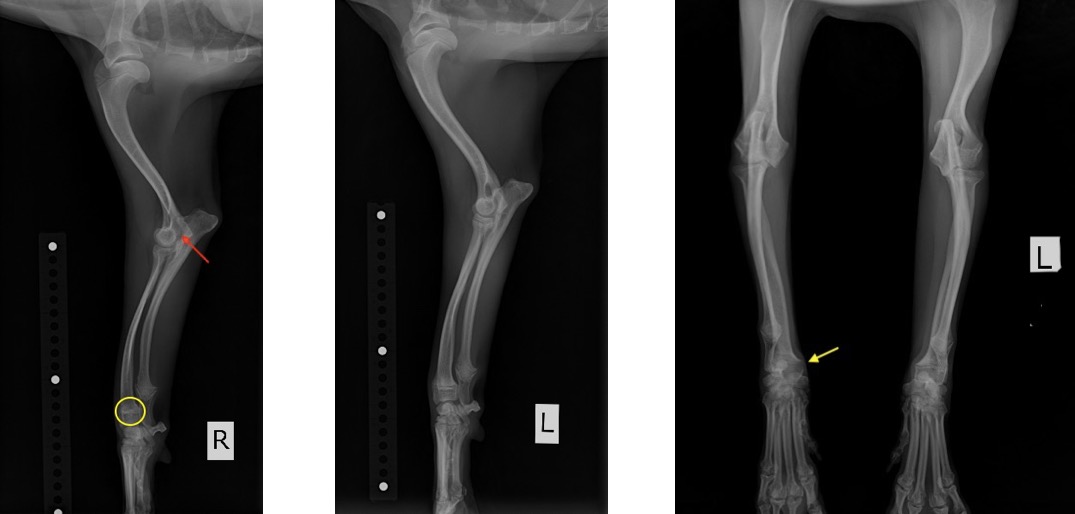

Mix (チワワ×プードル) 去勢雄 9ヵ月齢

1ヵ月前から右前肢を挙上させたり、歩行時における負重の低下を主訴に来院されました。

院内においても右前肢の挙上が認められ、単純X線画像検査を実施したところ、右側の橈骨遠位成長板領域の不透過性亢進、肘突起と上腕骨顆の間隙が広がっている所見が認められたため、橈骨遠位成長板早期閉鎖が疑われました。

この症例では、反対側と比較して橈骨の湾曲が顕著でなかったため、肘関節の整合性を優先し、尺骨の骨切りを実施しました。

前腕のLateral像とAP像 (黄丸と黄矢印:成長板の不透過性亢進 赤矢印:上腕骨顆と肘突起の間隙)